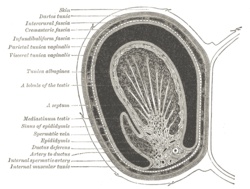

Vertical section of the testis, to show the arrangement of the ducts (internal spermatic artery labeled vertically at center) | |

Two or three of these accompany the ductus deferens, and supply the epididymis, anastomosing with the artery of the ductus deferens; others pierce the back part of the tunica albuginea, and supply the substance of the testis.

The internal spermatic artery supplies one or two small branches to the ureter, and in the inguinal canal gives one or two twigs to the Cremaster.